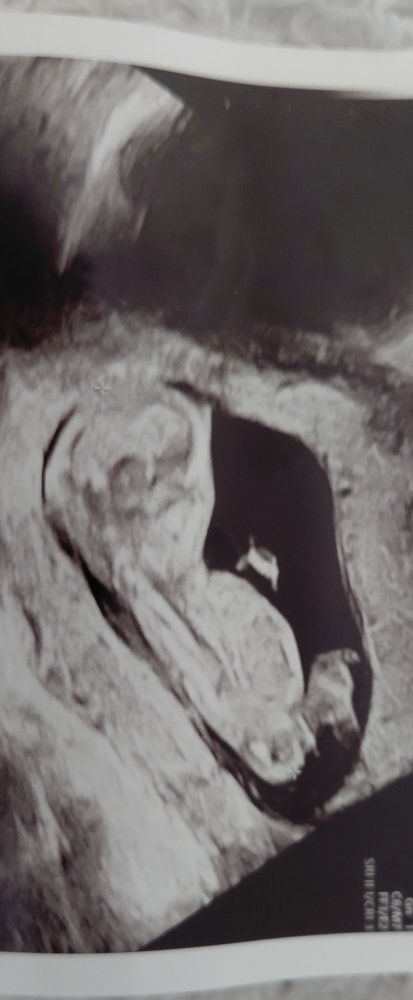

Was glaubt ihr, was für ein Geschlecht laut nub theorie ?